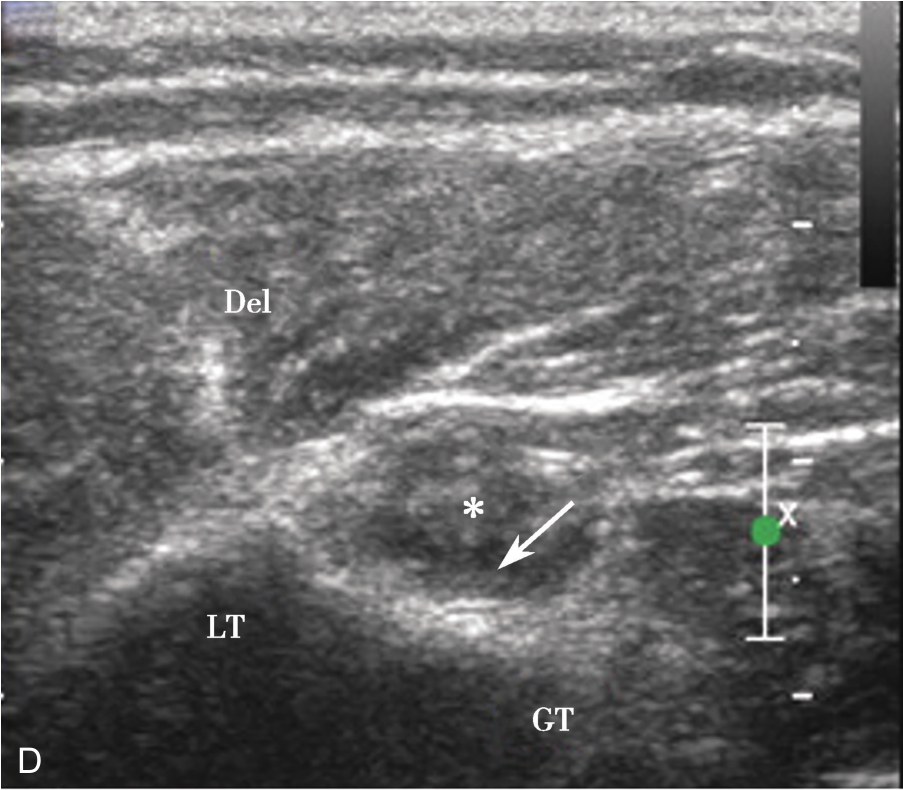

横放在肩关节前方,选择肩峰滑囊较厚或囊液较多处为靶目标(图2-1-2)。

▲ 图2-1-2 肩峰下-三角肌下滑囊炎超声图

星号:肩峰下滑囊增厚伴滑膜增生

平面内进针法,从内向外或从外向内引导针尖进入滑囊后进行药物注射(图2-1-3、图 2-1-4)。

▲ 图2-1-4 超声引导下肩峰下-三角肌下滑囊注射治疗超声图

箭头:穿刺针;星号:滑囊